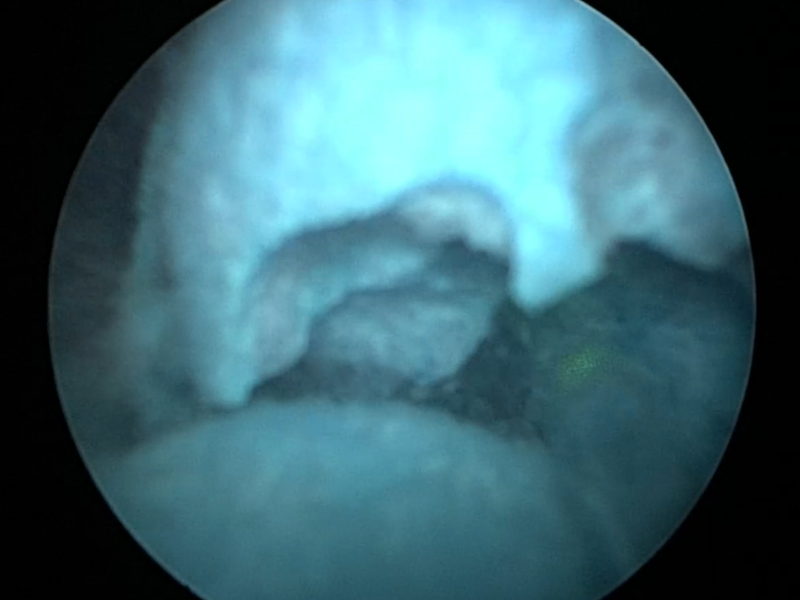

일반적으로는 전신마취로 진행되지만 골드만에서는 척추마취로도 안전하게 수술이 가능합니다. 마취 부담이 적고 회복이 빠르다는 것이 골드만의 큰 장점입니다.

골드만에서는 1박 2일 입원으로 다음 날 퇴원이 가능할 정도로 회복이 빠릅니다. 절개 범위가 작고 통증이 적어 일상 복귀가 빠른 것이 장점입니다.

미니 PCNL 기법을 사용해 절개 부위가 작고 통증도 비교적 적습니다. 흉터 걱정도 거의 없으며 대부분 잘 아물게 됩니다.

모든 결석 치료와 마찬가지로 재발 가능성은 있습니다. 그러나 PCNL은 결석을 직접 제거해 제거율이 높고 재발률도 낮은 편입니다. 시술 후 식습관, 수분 섭취 등 생활 관리가 중요합니다.